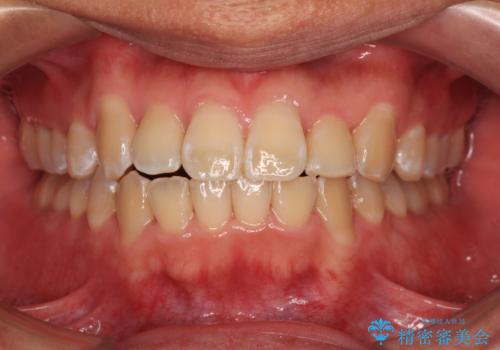

治療終了直後は上下前歯が接触していましたが、舌の突出癖がなかなか改善されず、終了時の口腔内写真撮影時には、既に上下前歯に隙間ができてしまいました。